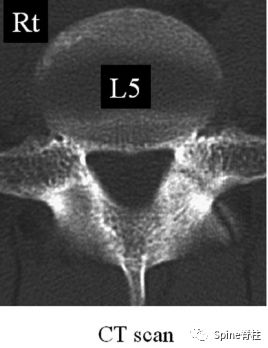

有研究发现磁共振上椎弓根出现T2高信号改变是青少年和儿童峡部裂的早期诊断征象。同时,存在椎弓根高信号改变也是保守治疗后能达到骨性愈合的良好预测指标(也就是说存在T2椎弓根右高信号改变的峡部裂患者,其峡部裂经保守治疗愈合的可能性大)

右上图为椎弓根高信号改变(+),右下图为(-)

左侧为椎弓根水肿阳性,右侧为椎弓根水肿阴性,有研究发现峡部裂伴随着椎弓根水肿,支具固定愈合率更高

Sairyo教授研究发现磁共振上椎弓根出现T2高信号改变是青少年和儿童峡部裂的早期诊断征象。同时,存在椎弓根高信号改变也是保守治疗后能达到骨性愈合的良好预测指标(也就是说存在T2椎弓根右高信号改变的峡部裂患者,其峡部裂经保守治疗愈合的可能性大)。

图:右上图为椎弓根高信号改变(+),右下图为(-)